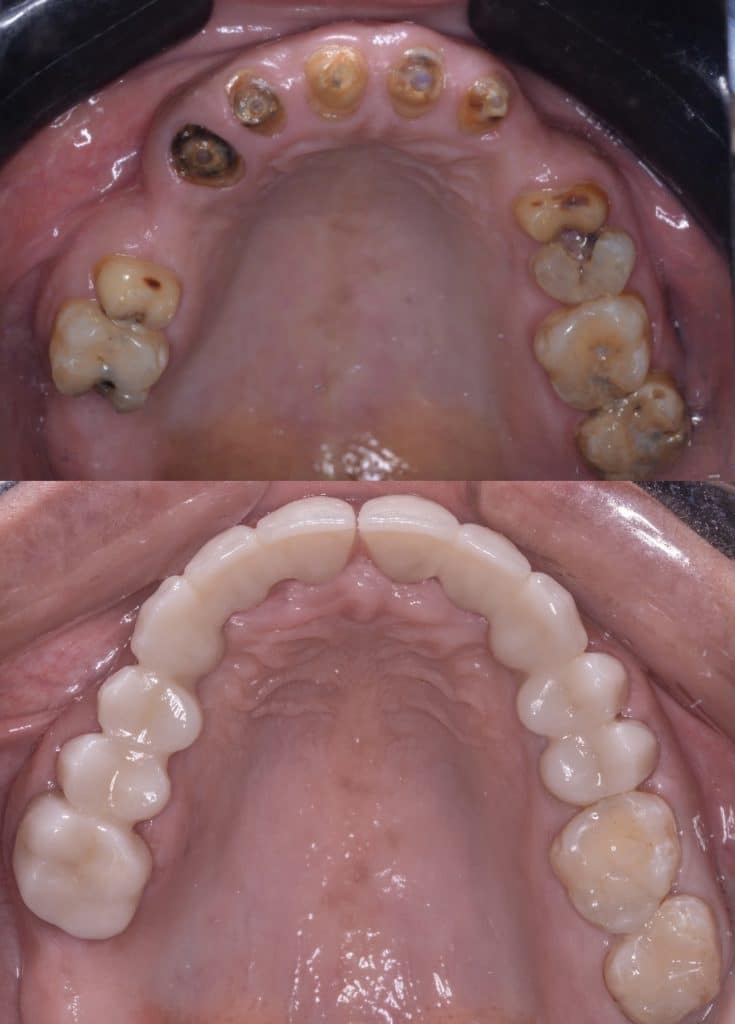

- Caries removal and Fiber post removal

- Endodontic retreatment for 7,8,9,10

- RCT for 4,5,13

- Fiber post placement and core build up in 4,5,13,7,8,9,10

- Composite filling were applied in 2,3,18,19

- Preparation of two bridges from 4 to 8 & 9 to 14 with Horizontal prep and subgingival chamfer finish lineNote missing teeth are 6,11,12

- After cementation of the bridges, rest seats were prepared for the RPD

- Metalic Rpd fabricated for class 2 mod 1 kindey classification

All impressions were done using additon silicone putty and wash (Coltene) to ensure good quality of impression and cast and maintain good dimensional stability for long time